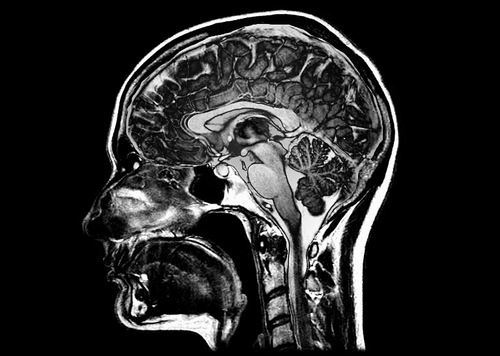

本报讯 一项对近5万份脑部扫描的分析,揭示了与衰老和神经退行性疾病相关的5种不同脑萎缩模式。该分析还将这些模式与吸烟和饮酒等生活方式因素,以及与健康状况和疾病风险相关的遗传和血液标志物联系起来。研究结果为开发神经退行性疾病早期阶段的检测方法带来希望。相关研究成果8月15日发表于《自然-医学》。

衰老不仅会让头发变白,大脑中的一些区域也会逐渐萎缩,发生微妙的解剖结构变化,这在核磁共振成像(MRI)扫描中是可见的。论文作者之一、美国宾夕法尼亚大学生物医学成像专家Christos Davatzikos说:“人眼无法获取与这种衰退相关的系统性大脑变化模式。”

然后,研究人员将得到的模型应用于近5万人的MRI扫描,这些人参与了各种衰老和神经健康研究。这项分析得出了5种不同的脑萎缩模式。研究人员将各种类型的、与年龄相关的大脑退化与这5种模式联系起来,尽管患有相同疾病的个体之间存在一些差异。